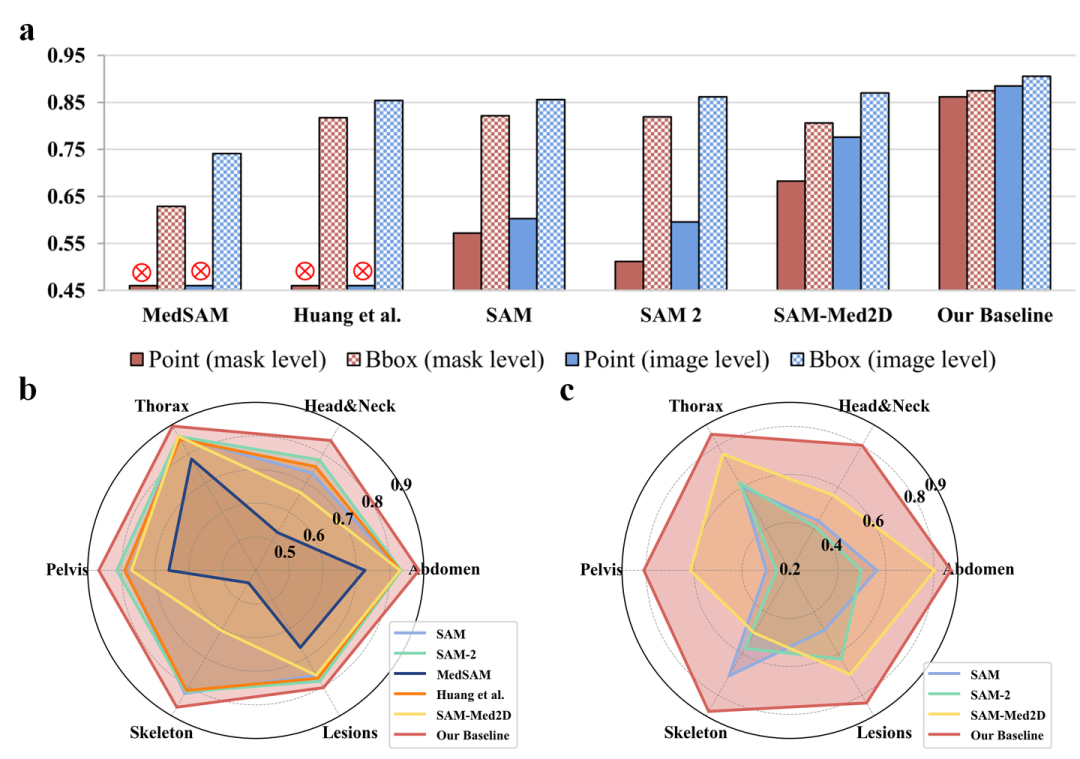

图4. IMIS-Net与其他交互式分割模型单次交互的性能比较

02 交互策略对模型的影响

图5. 不同交互策略对交互式分割模型的性能影响

IMIS-Bench 提供了一个统一的基准框架,对 IMIS-Net 和现有交互式分割方法进行了全面、系统的性能评估。实验表明,IMIS-Net 在多种模态和任务场景下显著超越现有技术。同时,团队还对多种交互策略对分割性能的影响进行了深入研究,为模型的优化和交互设计提供了宝贵的指导。